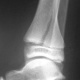

Через 1,5 месяца после наложения гипса.

Гипс надо снять. От физкультуры освободить на 1,5 месяца.